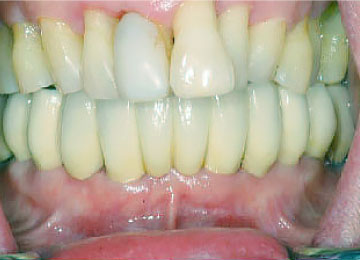

Имплантация зубов: фото "До" и "После"

Фото ДО

Фото ПОСЛЕ

Наведите для просмотра

All-on-4